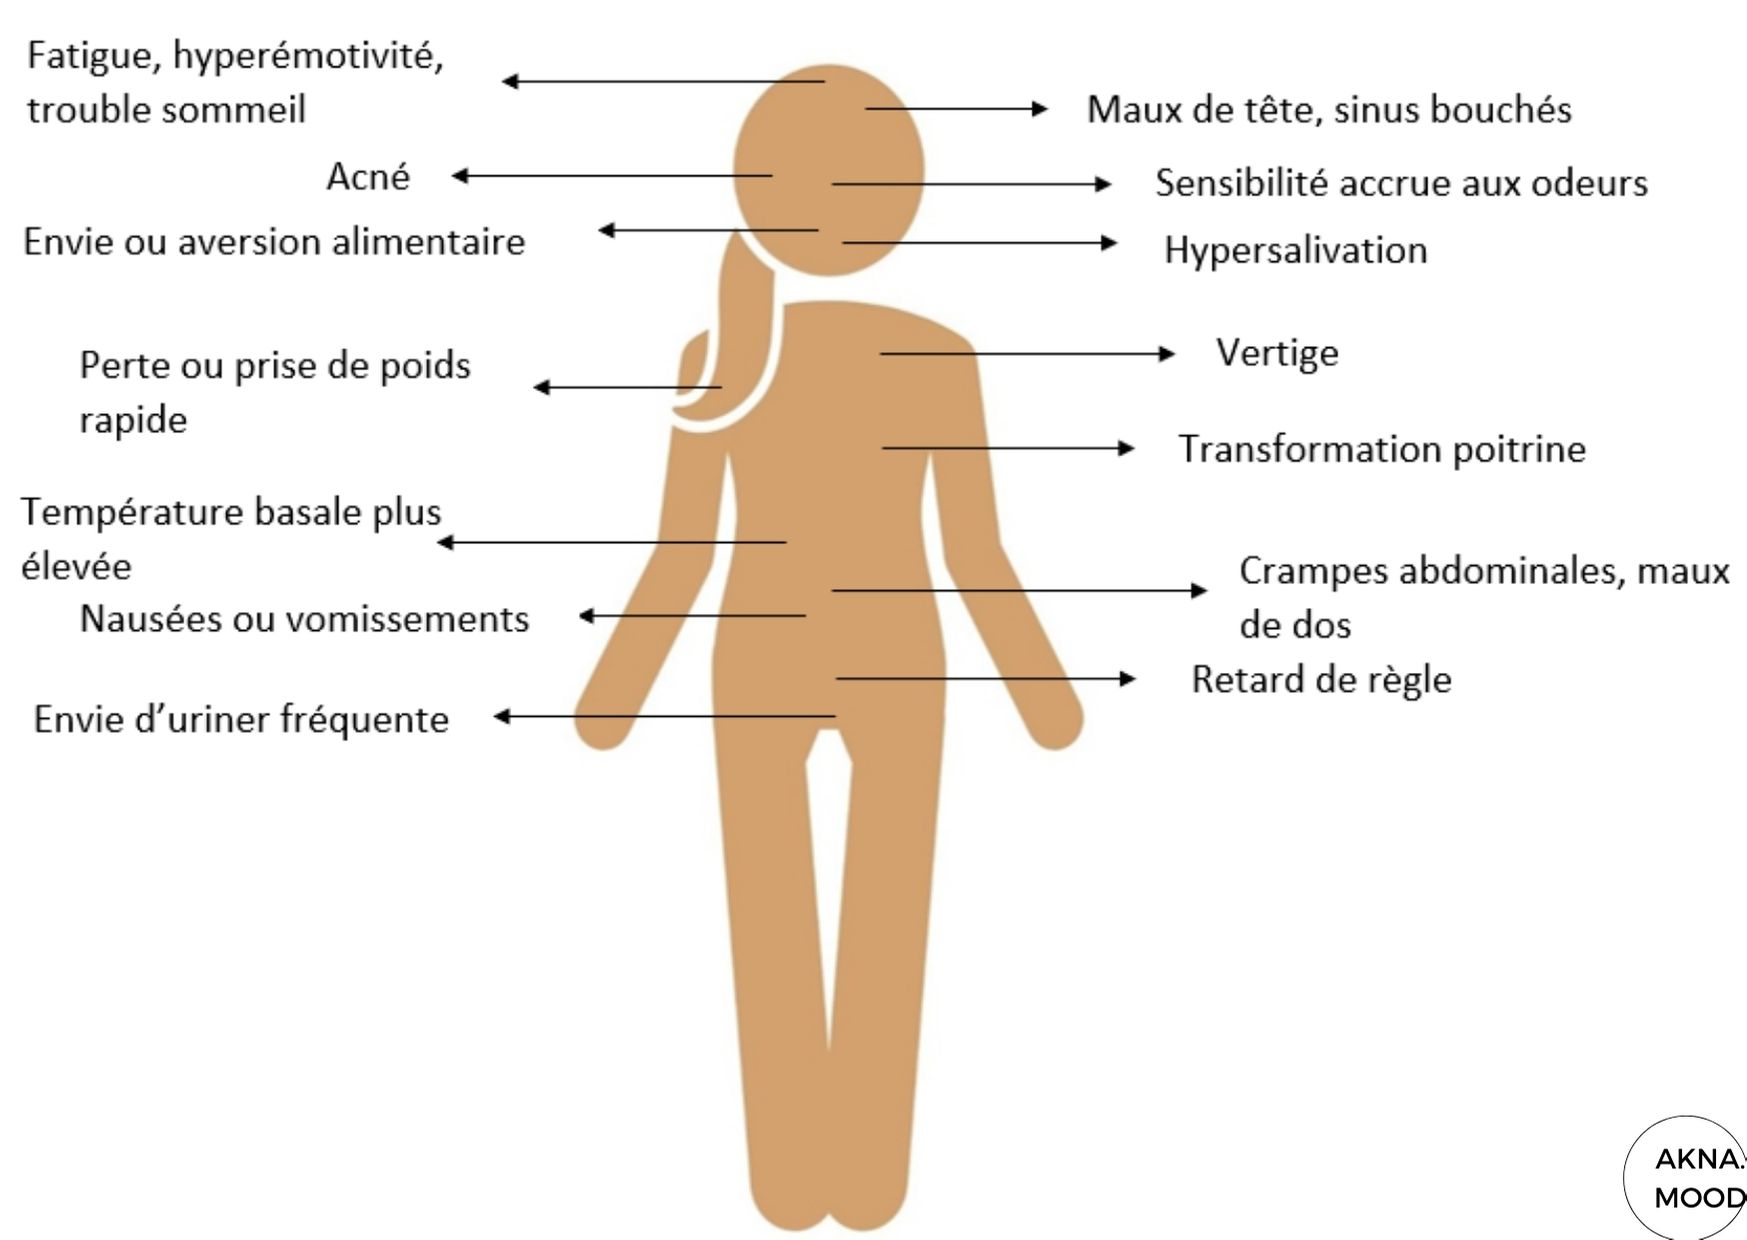

Au dernier trimestre il arrive parfois quun liquide jaune et. La grossesse appele aussi gestation humaine est ltat dune femme enceinte cest–dire portant un embryon ou un fœtus humain en principe au sein de lutrus qui est dit gravideEn gnral elle fait suite. Cest un dictionnaire pour les mots croiss et mots flchs. La pigmentation de larole se renforce pendant la grossesse 4. Oct 29 2020 Lhypertrophie des tubercules de Montgomery. De vos seins peut tre affecte sils sont comprims.

Hors grossesse son taux est infrieur. Jul 24 2020 Par exemple des seins plus gonfls avec un bombement des mamelons qui prennent une coloration plus fonce peuvent tre un signe de grossesse. Il est important de changer de soutien-gorge ds que nous notons que les seins commencent. Les petites glandes qui la parsment les tubercules de Montgomery sont hypertrophies et le rseau de Haller se dveloppe. Au dernier trimestre il arrive parfois quun liquide jaune et. Il ny a pas de tissu graisseux prmammaire.

Partir de la fcondation fusion dun ovule et dun spermatozode ou de la nidation implantation de lembryon dans l. Gonfler et que les tubercules ou boutons apparaissent ou grossissent. De la simple annonce charge dmotion. La fin de cette 4me semaine de grossesse 6 SA lapptit de la femme enceinte peut grandir et dans ce cas il est possible quelle prenne du poids. La mise en scne surprise avec une carte tout est possible pour lui annoncer la grande nouvelle.

Au dernier trimestre il arrive parfois quun liquide jaune et. Au niveau mondial le nombre total de cas est de 215 871 090 le nombre de gurisons est de 0 le nombre de dcs est de 4 492 602. Il ny a pas de tissu graisseux prmammaire. Jul 24 2020 Par exemple des seins plus gonfls avec un bombement des mamelons qui prennent une coloration plus fonce peuvent tre un signe de grossesse. Les petites glandes qui la parsment les tubercules de Montgomery sont hypertrophies et le rseau de Haller se dveloppe.